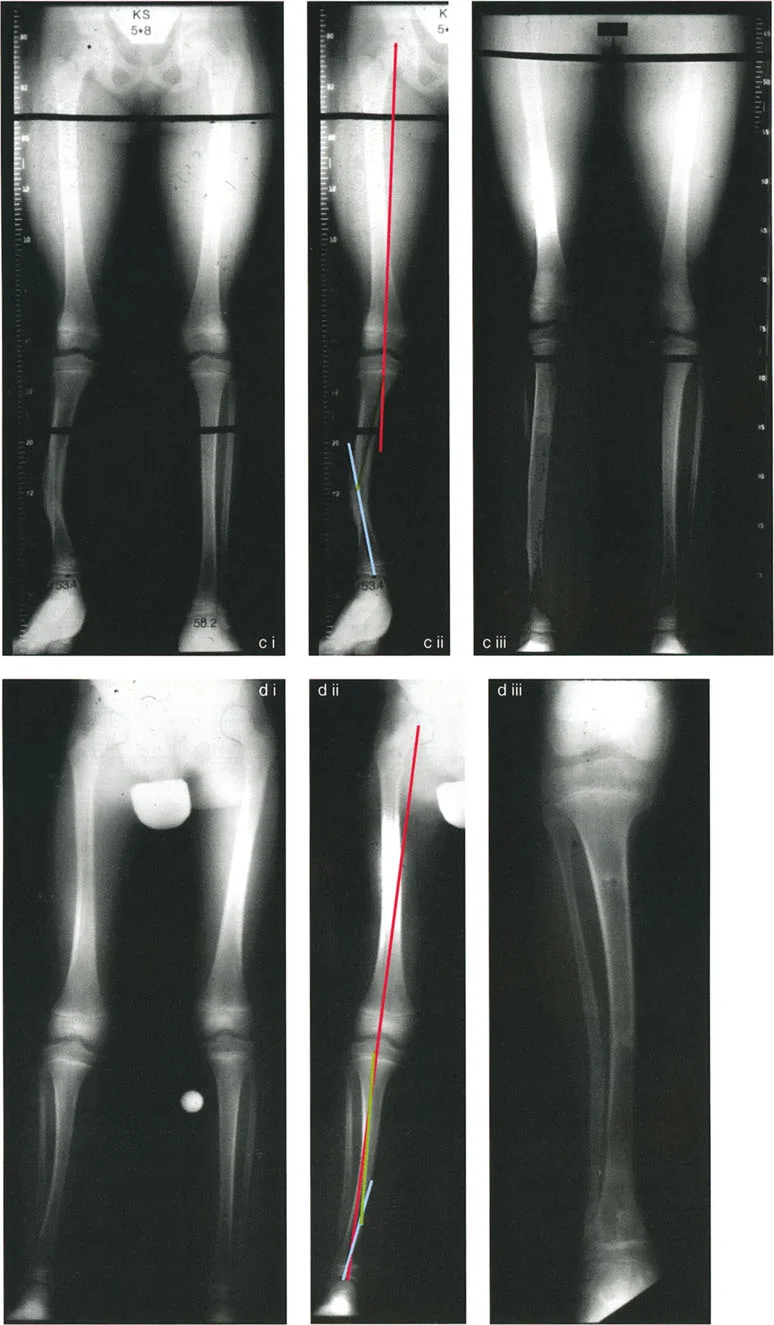

الأشعة السينية الكاملة للطرف (Full-Length Standing Radiographs)

هذه هي الأداة التشخيصية الأكثر أهمية. يتم الحصول على صور بالأشعة السينية للطرف بالكامل (من الورك إلى الكاحل) والمريض واقفًا، مع توجيه الرضفة (صابونة الركبة) للأمام مباشرة. هذا يسمح للدكتور هطيف بـ:

* تحديد المحور الميكانيكي: رسم الخطوط التي تحدد المحور الميكانيكي للطرف بدقة.

* قياس الزوايا: قياس الزوايا المختلفة للمفاصل (مثل زاوية الفخذ الوحشية القريبة mLPFA وزاوية الفخذ الوحشية البعيدة mLDFA) ومقارنتها بالقيم الطبيعية.

* تحديد موقع مركز دوران الانحراف (CORA): وهو نقطة التقاطع بين محاور العظم القريبة والبعيدة، والتي تمثل قلب التشوه.

مركز دوران الانحراف (CORA)

يعتبر CORA خاصية أساسية للتشوه في العظم. يُعرّف بأنه نقطة تقاطع خط المحور الميكانيكي (أو التشريحي) القريب وخط المحور الميكانيكي (أو التشريحي) البعيد.

مستوى قطع العظم (Osteotomy Level)

مستوى قطع العظم (الشق الجراحي) يقع بالكامل تحت سيطرة الجراح. تحدد العلاقة الهندسية بين مستوى قطع العظم، وACA، وCORA النوع الدقيق للتصحيح الناتج، وتحدد ما إذا كان سيحدث تشوه ثانوي غير مقصود (مثل الانزياح غير المرغوب فيه).

القاعدة الذهبية الأولى: القطع والمفصلة عند مركز الانحراف

عندما يمر كل من قطع العظم وACA مباشرة عبر CORA، يتم تصحيح التشوه الزاوي بشكل مثالي. يتم استعادة المحور الميكانيكي، ولا يوجد انحراف في المحور الميكانيكي (MAD)، وتبقى أجزاء العظم القريبة والبعيدة متوازية تمامًا. هذا هو السيناريو المثالي، والذي غالبًا ما يتحقق بقطع عظم وتدي بسيط (فتح أو إغلاق) عند قمة التشوه.

القاعدة الذهبية الثانية: المفصلة عند مركز الانحراف والقطع بمستوى مختلف

في بعض الأحيان، قد يكون قطع العظم مباشرة عند CORA غير ممكن سريريًا بسبب سوء حالة الجلد، أو وجود أدوات جراحية سابقة، أو مشاكل في جودة العظم في منطقة الكردوس/الجذع. إذا بقي ACA عند CORA، ولكن تم إجراء قطع العظم عند مستوى مختلف (أقرب أو أبعد عن CORA)، فسيتم تصحيح التشوه الزاوي بالكامل. ومع ذلك، ستنزاح نهايات العظم عند موقع قطع العظم بالنسبة لبعضها البعض.

* النتيجة السريرية: يؤدي هذا إلى "نتوء" أو تعرج في المحور التشريحي، لكن المحور الميكانيكي العام وتوجيه المفصل يظلان متوائمين تمامًا.